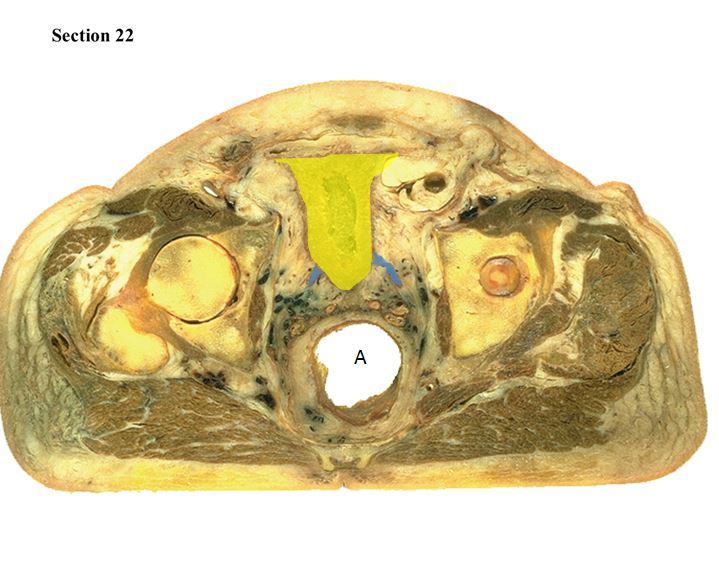

8

Q

The yellow organ is the ___ and the blue organs leading to it are the ___

A

urinary bladder

left and right ureters